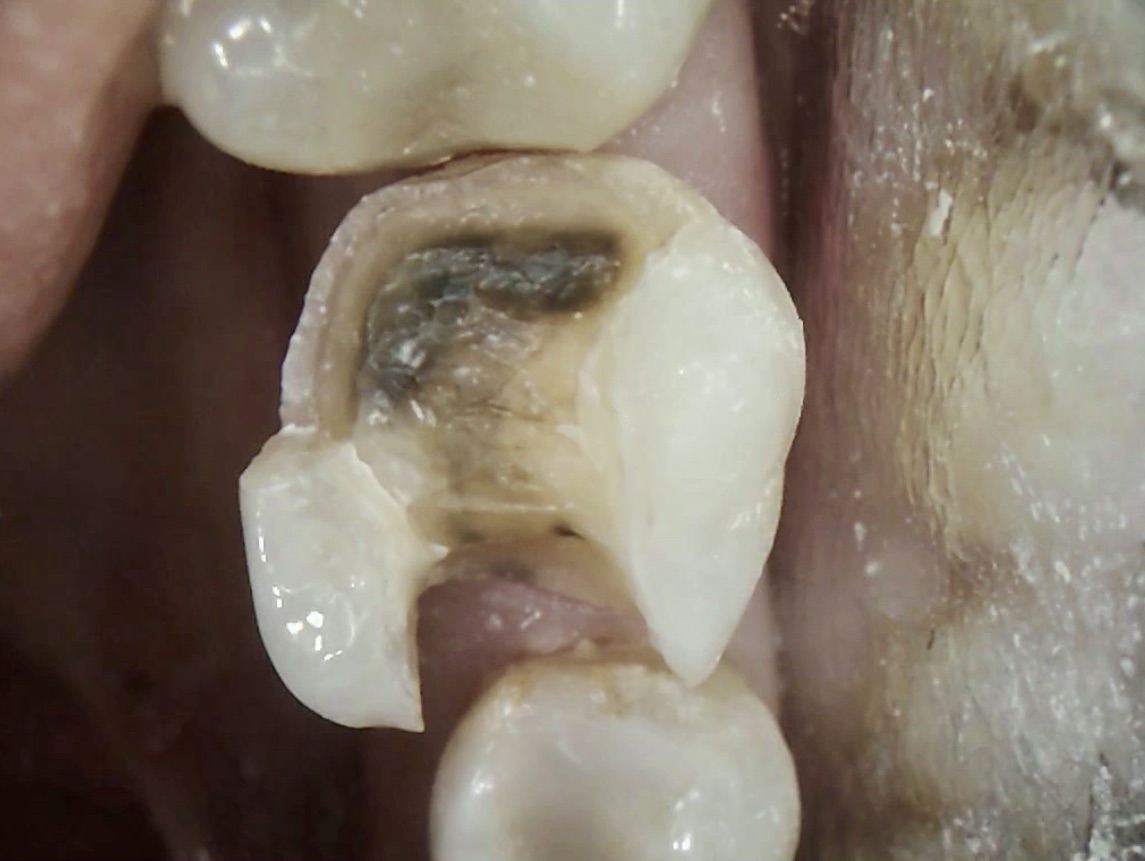

Broken Tooth with Cavity